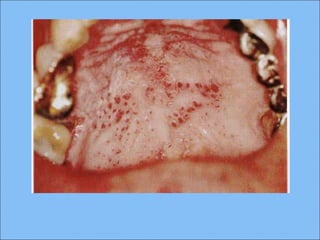

CLÍNICAMENTECLÍNICAMENTE

Tres tipos: reticular, atrófico y erosivo

Atrófica:

 Placas rojas y estrías blancas muy finas

 En ocasiones hay ardor, hiperestesia

 Cuando se presenta en encía se puede confundir

con gingivitis descamativa.

Erosiva:

Región ulcerada

Placa fibrinosa o seudomembranosa sobre la úlcera

Al examen cuidadoso se identifican estrías

queratósicas en la periferia del sitio erosionado.

El dolor es más frecuente en la mucosa yugal.